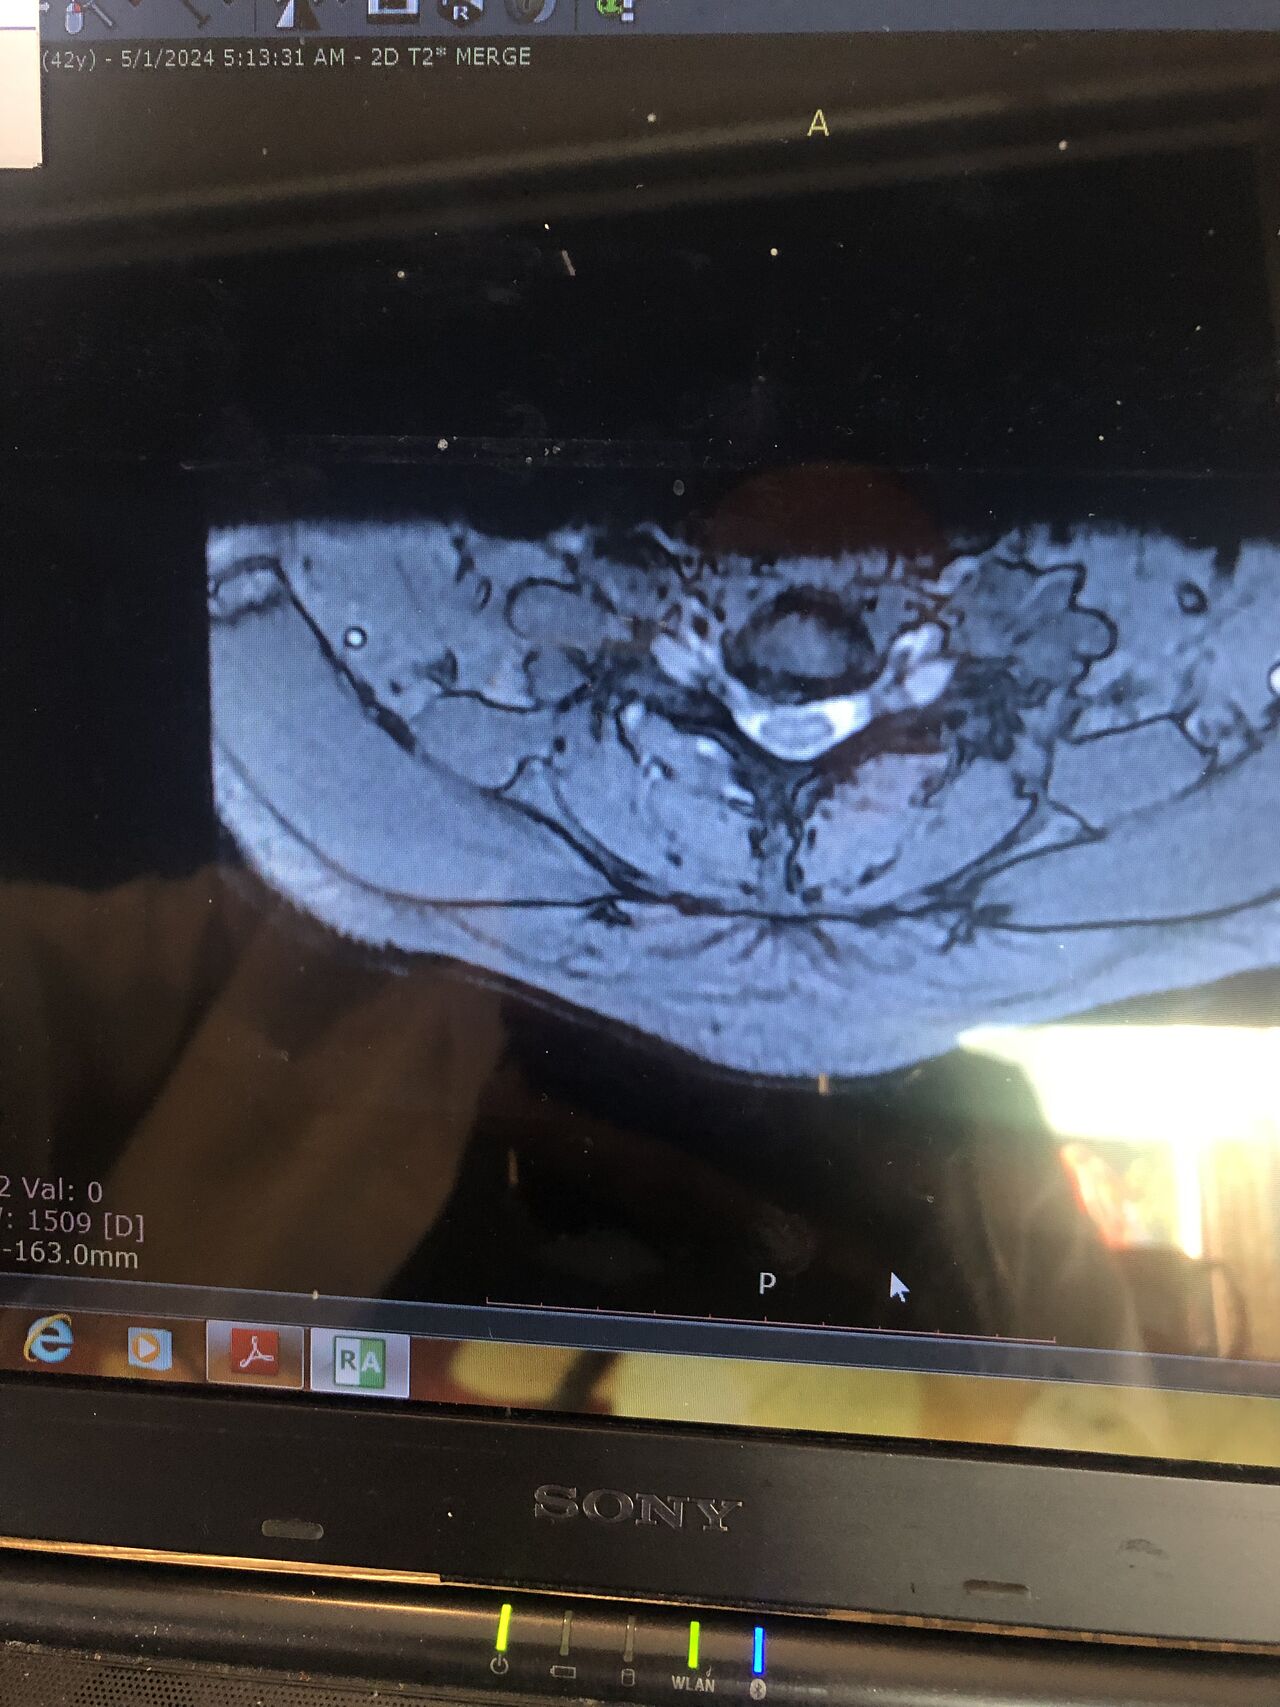

Case 9

42 years old female presented to my clinic yesterday on May15/2025 with chronic Low back for 2 yrs. She is from afghanestan and arrived to tehran 3 month ago. Visited pain specialist 3 months ago who just did PPD test and gave her Anti TB medication. In examination just had severe focal khyphosis from L3 to L5 without any tenderness. Her mri was done 2 months ago. Report is in Farsi and mentions of paraspinal puss/ fluid collection esp in psoas muscles, with extension of fluid collection to R pelvic region. Had 2 site of severe canal stenosis due to previous fractures of L3,4,5 and movement of fractured bones to the canal with complete distractions of those levels discs with fusion of L3 to L5

I ordered C T scan of lumbar and pelvic MRI / chest x r and reffered her to neurosurgon and infectious disease specialist to get full assessment and possible hospitalized for biopsy and surgery